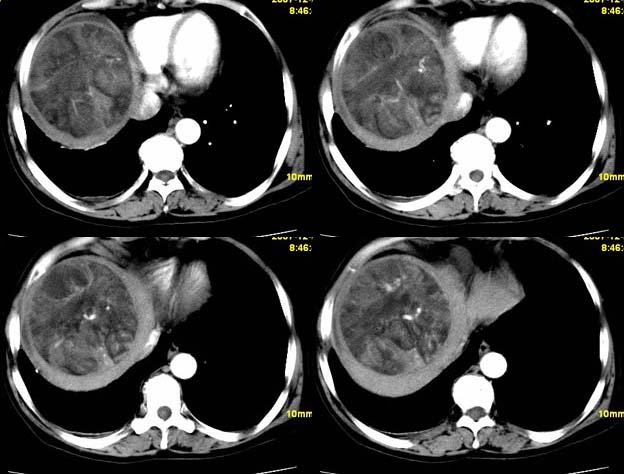

增强

支持;肝aml-------脂肪成分,中心血管征,延时强化.